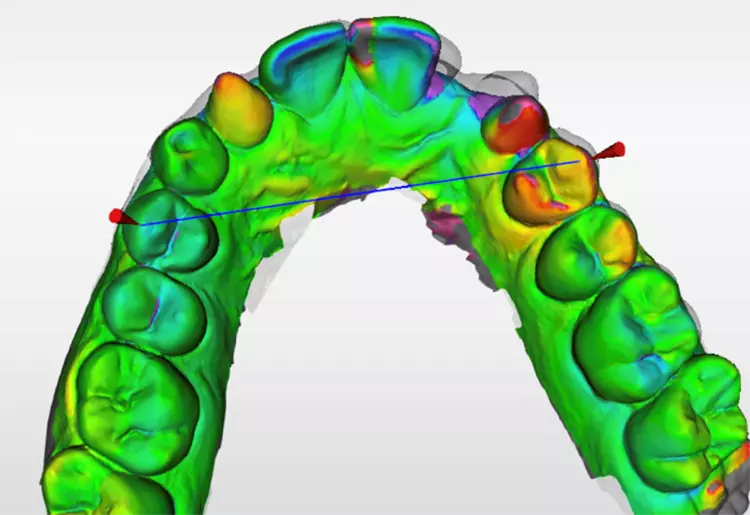

Mit dem Einsatz der Analyse-Software „OraCheck“ unterstützt Frau Dr. Frederike Fehrmann, Heuchelheim, ihre Befundung sowie zur Differenzanalyse (Abb. 6). Die OraCheck-Software, seit 2013 erhältlich und mit dem Cerec-System ab der Omnicam anwendbar, gewinnt neuerdings durch Integration in die Primescan zunehmend an therapeutischer Bedeutung. Komplexe Vergleiche unterschiedlicher, dreidimensionalen Scans ermöglichen eine Kontrolle der Behandlungsergebnisse, detektiert Stellungsveränderungen der Zähne während einer KfO-Behandlung, kontrolliert Parodontal-Therapien, den Volumenaufbau in der Chirurgie, z.B. bei der Vorbereitung des Implantatlagers. Fehrmann

Mit zeitversetzten Intraoralaufnahmen macht die Software auch Abrasionen, Zahnwanderungen, Funktionsstörungen und Gewebeveränderungen sichtbar. Die Software ist ein objektives Hilfsmittel für Behandlungsentscheidungen und zur Dokumentation von Veränderungen.